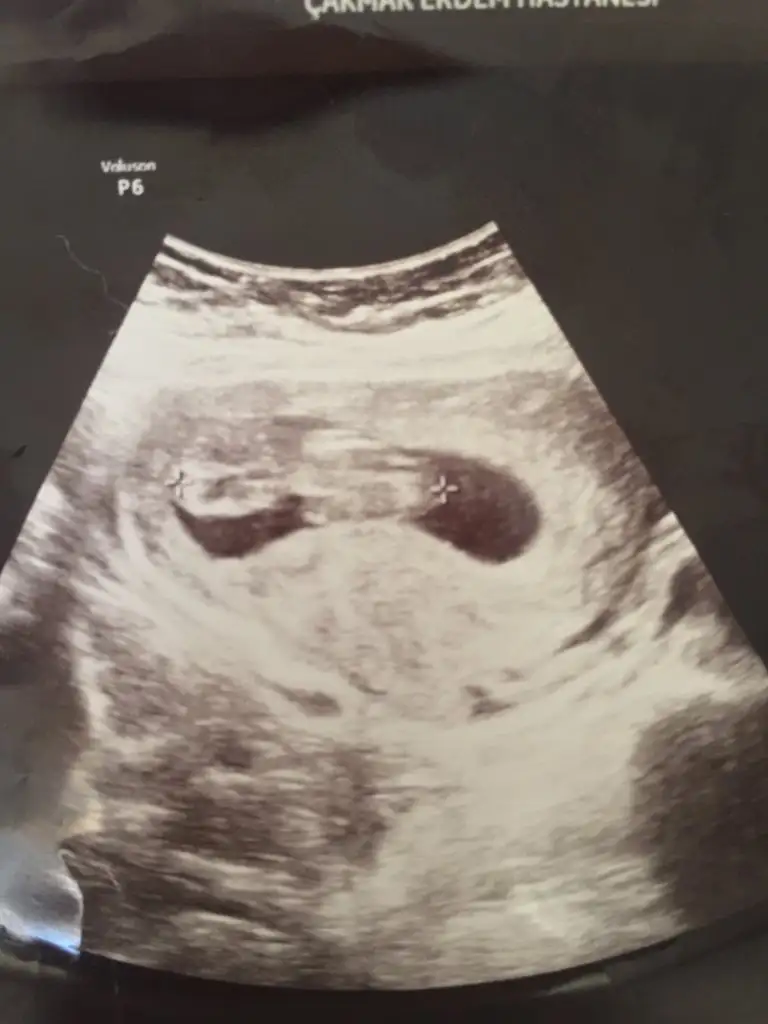

Atti canim bi bak hele Insallah dr yanilmistirUSG bakabilirmiyim kaç haftalık birde

18+ da nub olmaz cnm baya büyükmüş Minnoş hayırlısı olsun ne güzel prenses geliyormuş rabbim korusunAtti canim bi bak hele Insallah dr yanilmistir

Erkek

Yaa çıkıntı yukarı doğrumu sizce

Bence evet ama 11 12 13 haftalar gerekliYaa çıkıntı yukarı doğrumu sizce

Erkek gibiMerhaba herkese Ikra meyra bebegimin ultrosan fototsunu attim banada yorum yapabilir misin lutfen 11+3

Net değil olursa 12-13 hafta tekrar paylaşınSelam arkadaşlar, biz de bugün 11+4 olduk. Cinsiyet tahmini alabilir miyiz ☺